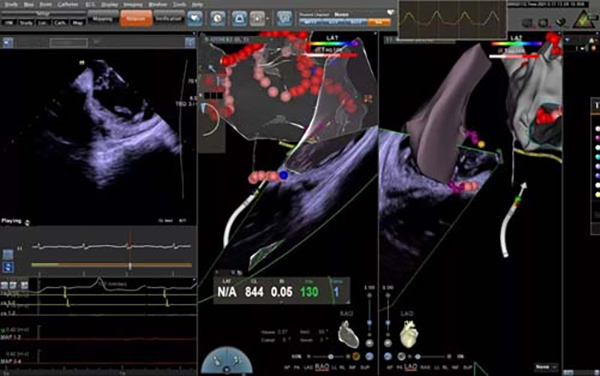

The operation was used the classic 2C3L way. After zero rays penetrated the atrial septum under the guidance of ICE catheter, the 3D model of the left atrium was quickly and accurately established. The ablation of pulmonary vein antrum isolation + atria roof line, mitral valve isthmus line and tricuspid valve isthmus line were completed with high power. Atrial fibrillation was successfully terminated and the rhythm was converted to sinus rhythm. High power ablation greatly shortened the operative time, reduced the pain and improved the cooperation of patients during operation.

ICE significantly reduced the amount of X-ray exposure and avoided the use of contrast agents. During the operation, the pericardium was monitored in real time to make sure serious complications such as pericardial tamponade could be found at the earliest time possible, ensuring the safety and effectiveness of the operation to the greatest extent.

During ablation

Ultrasound real-time monitoring

2. ICE-guided ablation during operation. Compared with atrial fibrillation ablation under the traditional X-ray and 3D mapping system, ICE can provide a comprehensive and 3D view of the structure of heart cavity, and locate the ablation catheter more accurately. The real-time display of catheter attachment significantly improve the success rate of surgery. Changes in the cavity during the operation can be monitored in real time, and complications such as pericardial effusion can be found at the earliest time possible, which improves the safety of surgery. ICE can effectively reduce the amount of X-rays and reduces the radiation injury to surgeons and patients. The ICE-guided atrial septum puncture can intuitively indicate the optimal puncture position to perform safe and effective puncture. It can accurately locate the pulmonary vein opening and provide a reliable and effective plan for precise ablation. This technique can greatly improve the efficacy and safety of ablation in elderly patients with atrial fibrillation.